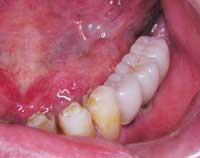

| Before | After |